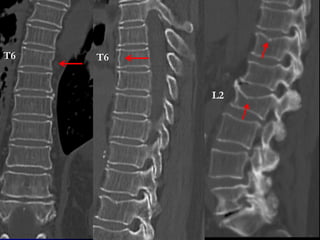

1 2 3 4

WHICH PATIENT HAS ACUTE FX WITH SUBSEQUENT FUSION?

3

T6 T6

L2